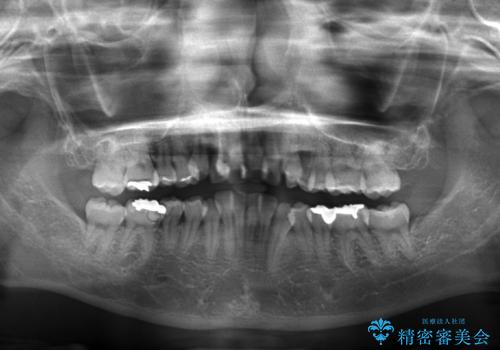

- 前歯のデコボコと上顎の前突感による口の閉じにくさを気にして来院された患者様です。

目立たない装置を希望されたので、上顎が裏側装置のハーフリンガルを選択し、上下左右の小臼歯(計4歯)を抜歯して矯正治療を行うこととしました。

治療期間の目安は3年~3年半でしたが、咬み合わせにより上顎のスペースがなかかな閉じきらず、治療期間が長期化してしまいました。

期間はかかったものの、口元の張り出し感や歯のデコボコが解消され、患者様には大変満足していただけました。